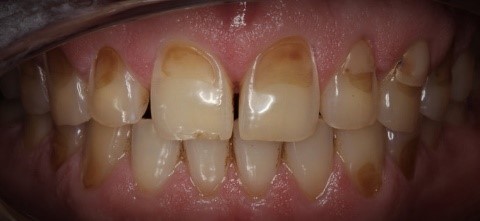

Tanda-Tanda Erosi Gigi

Anda mungkin mengalami erosi gigi jika Anda memperhatikan tanda-tanda berikut:

• Perubahan Warna: Gigi mungkin terlihat lebih kuning karena enamel terkikis dan dentin yang berwarna lebih gelap terpapar.

• Sensitivitas: Gigi mungkin menjadi lebih sensitif terhadap suhu panas, dingin, atau makanan dan minuman manis.

• Gigi Lebih Halus atau Tipis: Enamel yang terkikis dapat membuat gigi terasa lebih halus dan terlihat lebih tipis atau transparan di ujungnya.manis.